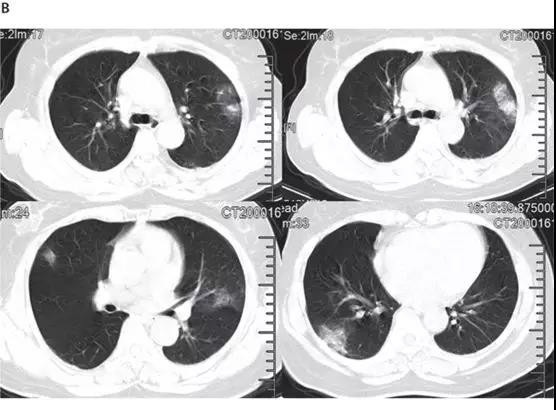

非ICU患者的代表性胸部CT檢查表現(xiàn)為雙側(cè)毛玻璃樣混濁和亞段實變(見下圖)。